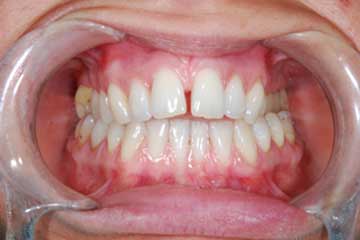

Con protesi fissa superiore e protesi fissa inferiore

I denti irrecuperabili dell'arcata superiore ed inferiore del paziente di anni 65

sono stati sostituiti da 10 impianti, cioè protesi radicolari endo-ossee che sostengono le protesi fisse superiore ed inferiore.